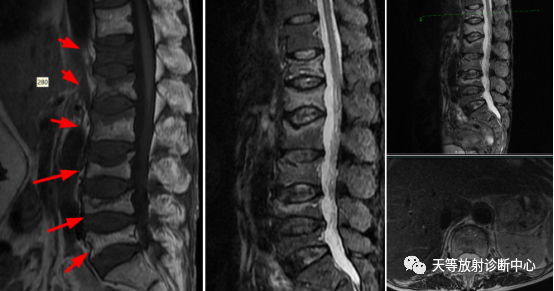

▲女性,66岁。腰椎多个椎体压缩性骨折,为骨质疏松脆性压缩性改变,椎体内未见骨质破坏,未见软组织肿块,各个附件骨质信号无异常。本病例为腰腿痛病人,骨质疏松伴多发椎体脆性压缩性骨折,新旧不一,诊断中警惕观察排除是否多发性骨髓瘤。